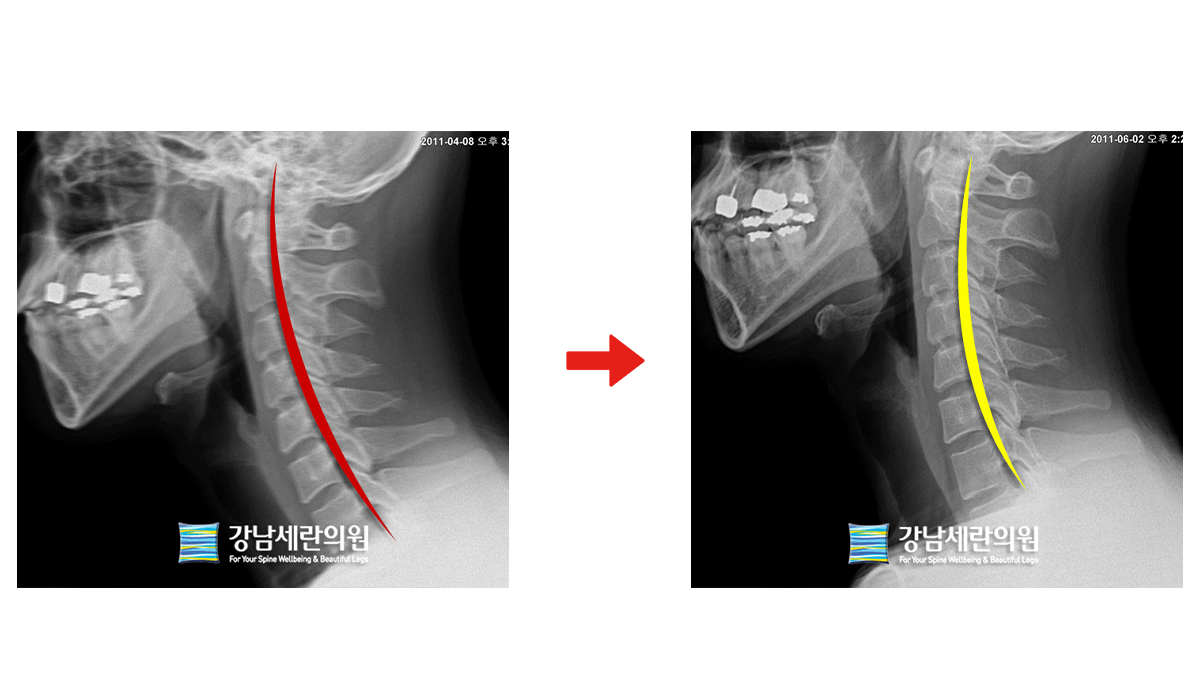

#일자목

일자목 치료 전 ▶ 일자목 30회(3개월) 치료 후